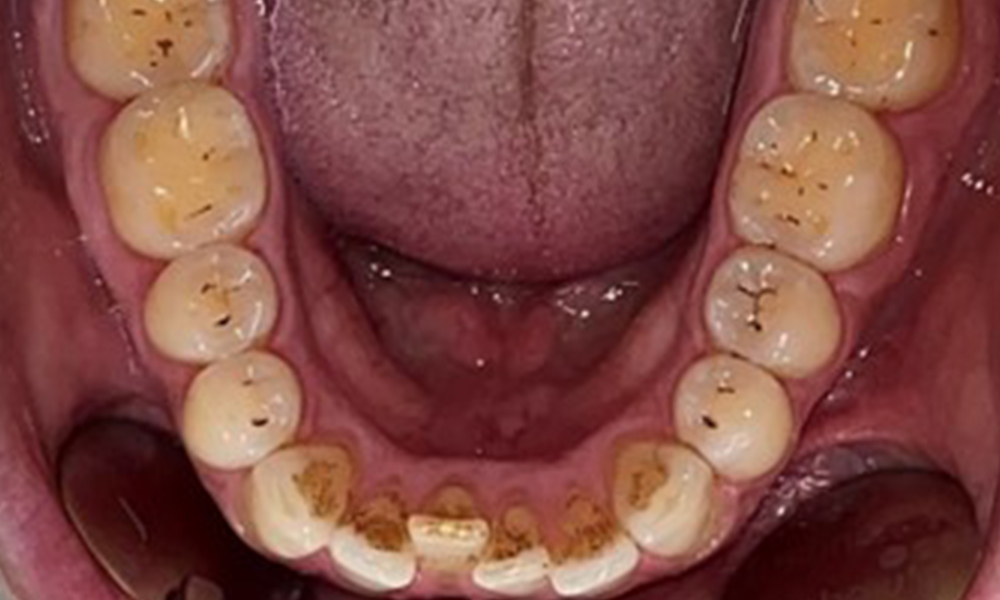

Dental zeigt sich ein vollbezahntes Gebiss mit 28 Zähnen. Auffällig sind Erosionen und Attritionen

(Abb. 4, Abb. 5). Der Patient trägt seit vielen Jahren nachts eine Schiene mit adjustiertem Aufbiss aufgrund Bruxismus. Die Erosionen sind auf den langjährigen Konsum isotonischer Getränke zurückzuführen. Parodontaler Knochenverlust und aktive kariöse Läsionen sind nicht vorhanden.